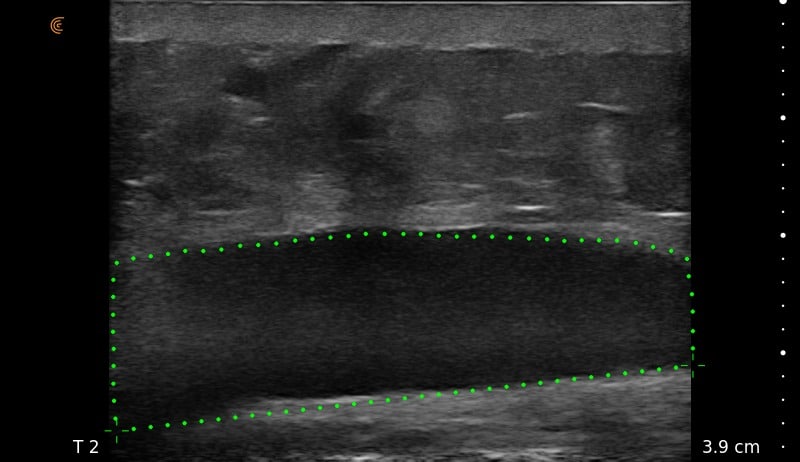

Ultrasound Imaging is very useful clinical tool to assess patient’s anatomy. In the past, ultrasound imaging was done primarily by radiologists, but is now being employed by many clinical specialties. Ultrasound use by Plastic Surgeons, however, is relatively new. Dr. Wigod has found ultrasound imaging to be a particularly valuable addition to physical exam and provides this service to his patients. Ultrasound imaging is especially useful to assess breast implants for problems such as ruptures, capsular contracture, and fluid collections. Dr. Wigod also uses ultrasound to examine other body areas and to help guide nerve blocks. Surgeon performed ultrasound does not replace radiologist performed imaging and is not for cancer screening.

For more examples of ultrasound images, go to the Breast Ultrasound Images Gallery.